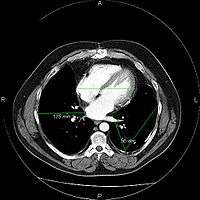

Most PACSs handle images from various medical imaging instruments, including ultrasound (US), magnetic resonance (MR), Nuclear Medicine imaging, positron emission tomography (PET), computed tomography (CT), endoscopy (ES), mammograms (MG), digital radiography (DR), computed radiography (CR), Histopathology, ophthalmology, etc. Additional types of image formats are always being added. Clinical areas beyond radiology; cardiology, oncology, gastroenterology, and even the laboratory are creating medical images that can be incorporated into PACS. (see DICOM Application areas).